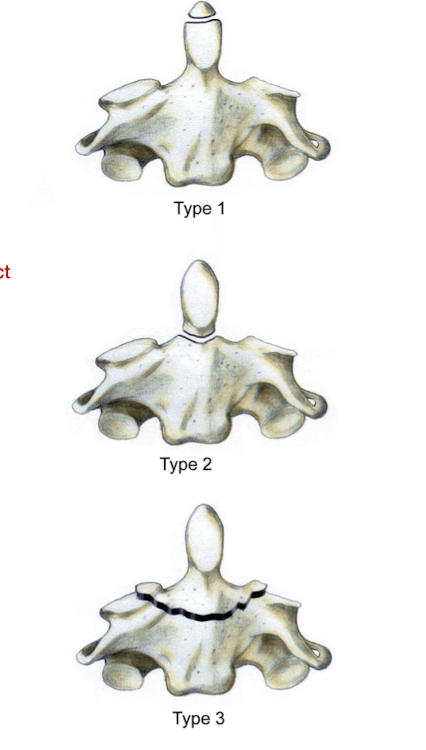

What are the 3 types of Odontoid Fractures?

Type 1:

Avulsion of the Hip

Type 2:

At junction of dens on the body of the axis

Type 3:

Below the junction of the dens

Fracture of the Axis: Dens

Which of the 3 types of Odontoid Fx is the most difficult to heal?

Why?

Type 2

Intact transverse and alar lig w poor bony contact